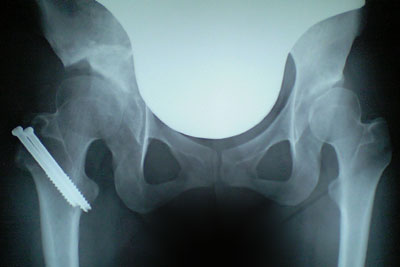

レントゲンとCTを撮影。

レントゲンを見ると、28日の時と大きな違いは(素人目には)見られませんでしたが、以前より着実に骨の癒着は良くなっているそうです。

そして独歩の許可が下り、術足に体重100%加重可能になりました。

今日はデジカメを忘れてしまい携帯カメラで撮影。